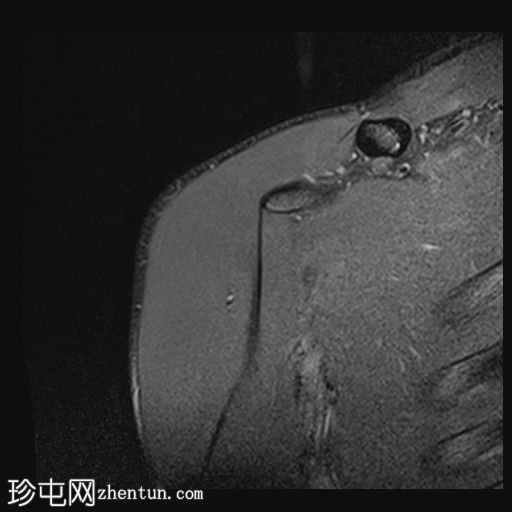

轴位PD序列

脂肪抑制序列

前下盂唇撕脱,骨膜附着完整,提示软性Bankart损伤。

肩胛盂下韧带前束在盂肱关节附着处断裂,符合GAGL(肩胛盂下韧带)的特征,盂肱关节下方可见关节囊外积液,并伴有盂唇旁囊肿。